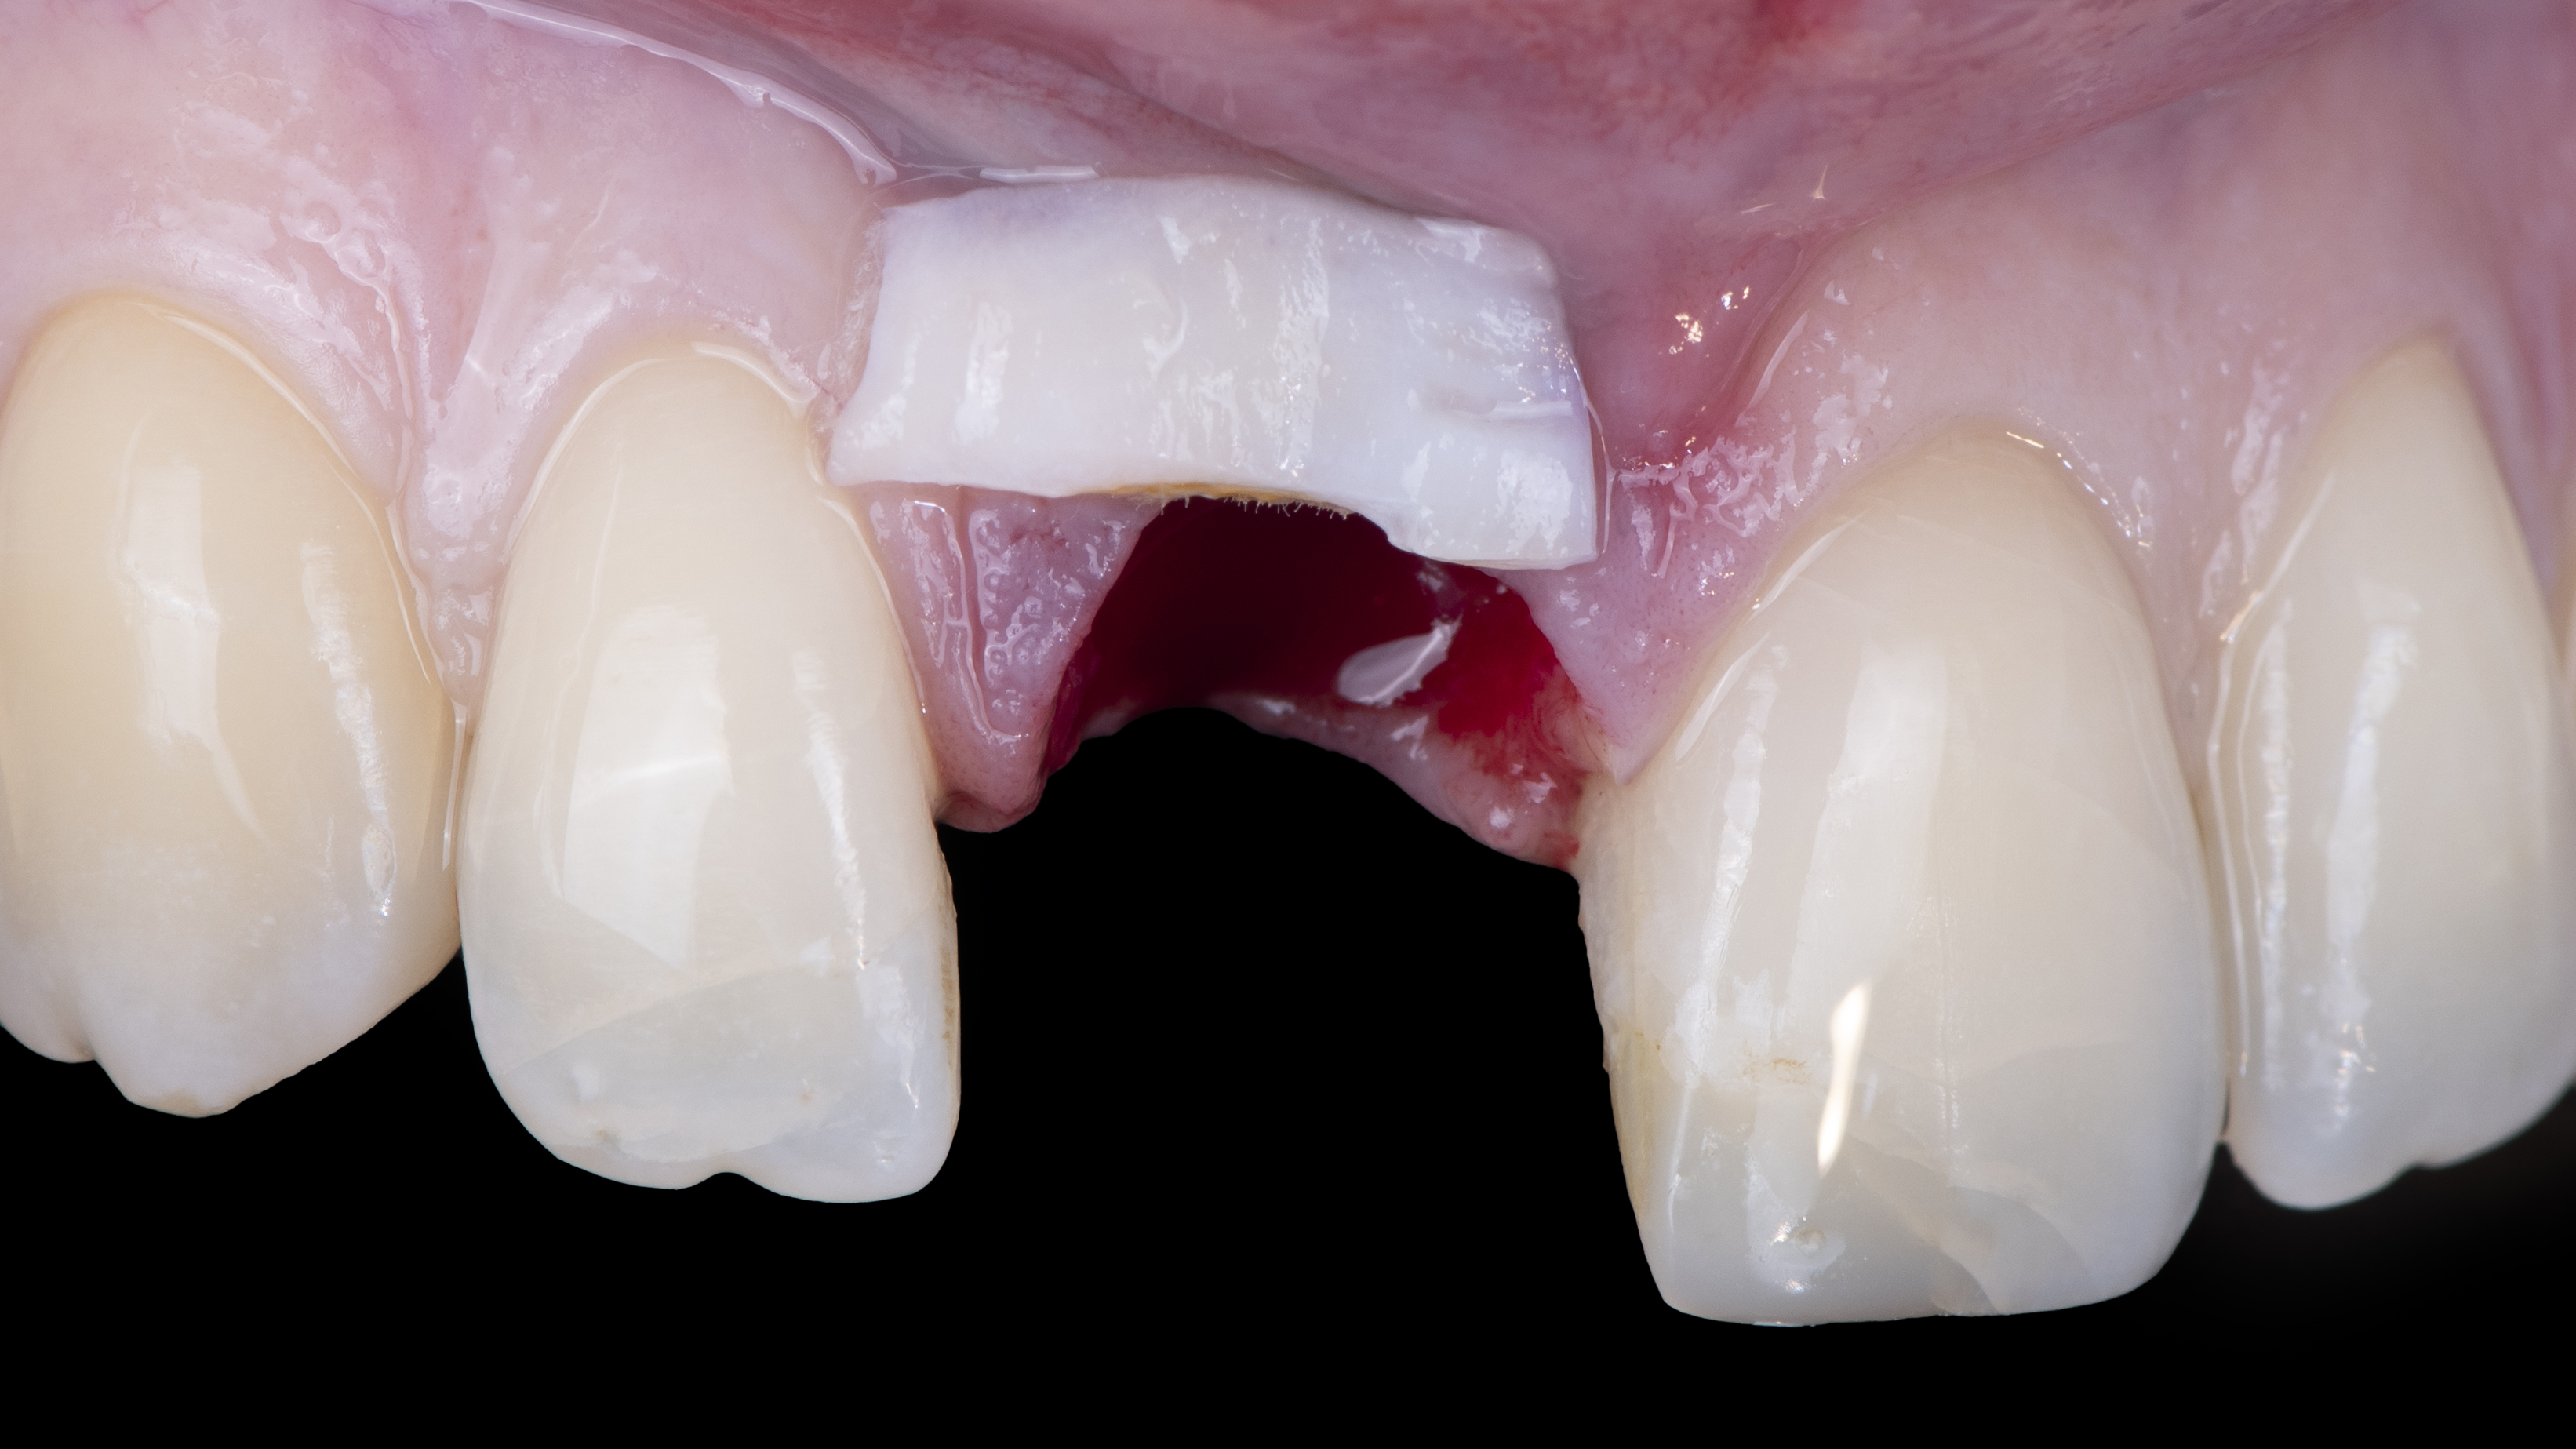

Une copie de la couronne de la patiente est imprimée et évidée pour permettre de la positionner correctement. Elle est ensuite solidarisée à un pilier provisoire vissé dans l’implant. Ceci nous permet ensuite d’ajuster le profil d’émergence (Photo 12).